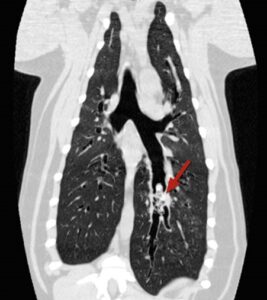

- Lungs are more complicated and may require specialist investigation and treatment in the form of a CT scan and removal using the flexible bronchoscope. Occasionally these cases may require major surgery to open the chest and remove an entire affected lung lobe

CT scans showing different views of the same dog’s chest with a grass seed lodged in the lungs (the grass seed is arrowed)